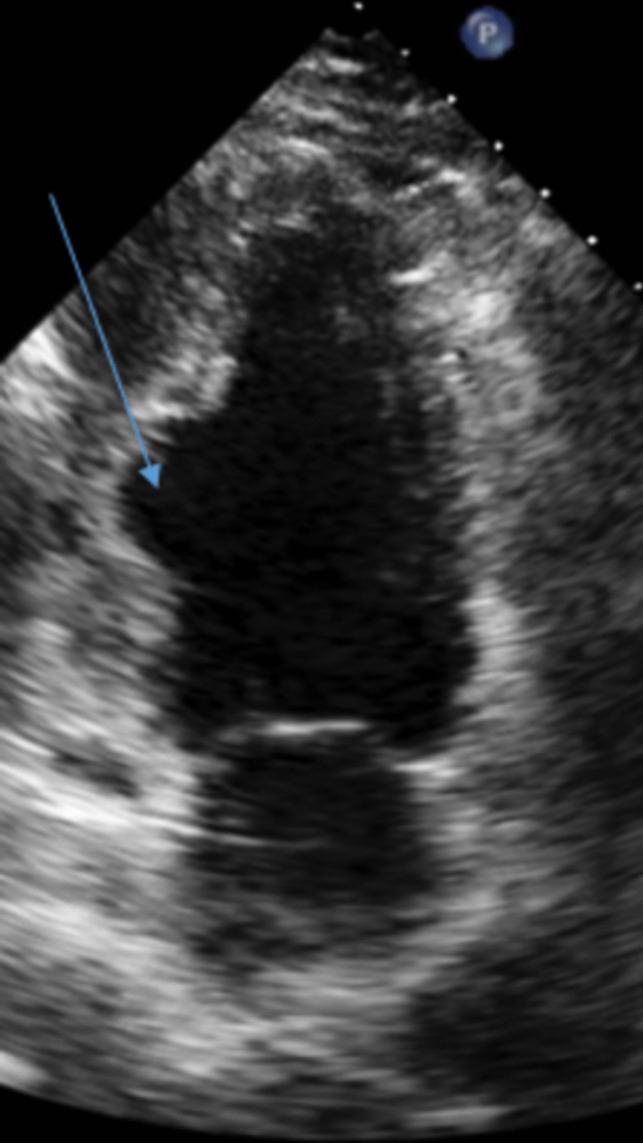

Purpose of review: The purpose of this review is to highlight the utility of echocardiography in the diagnosis and management of cardiomyopathies.

Recent findings: Echocardiographic parameters function synergistically to guide decision-making ranging from early detection of disease and screening to risk stratification of complex disease. The collective wealth of information available from 2D/3D assessment, Doppler, diastology and strain makes echocardiography an invaluable decision aid.